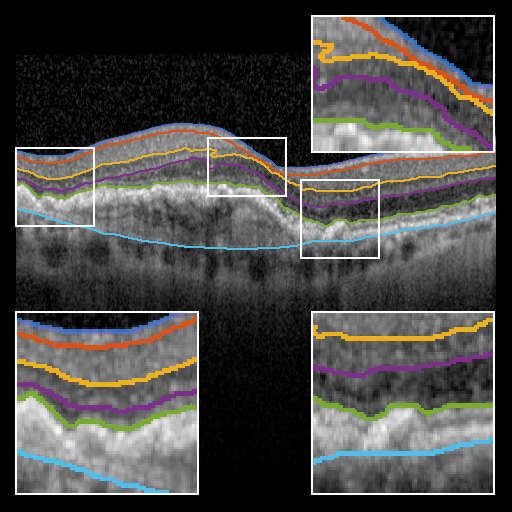

To evaluate BRU-net, we compare it with the 3D methods of Dufour [5], Chen et. al. [4], and the 2D method of Mayer et. al. [12] on the same dataset. Additionally, we train a traditional U-net configuration [14] using the procedure described above. Fig. 3 provides a qualitative comparison of the results.